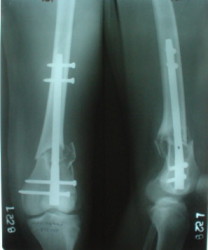

Отправитель: Alexander Chelnokov 27 Декабрь 2003, 21:34

Sorry but I've just prepared postop images - attached. A solid 13 mm nail was used. A few degrees of recurvation appears to be which i missed on image intensifier. I'm still uncertain about

advantages/disadvantages of ante/retrograde nailing for such fractures.